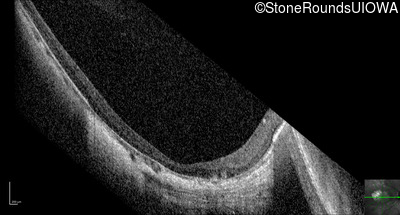

Optical Coherence Tomography - Right - 10/180

Exemplar / OCT Stack

OCT Stack